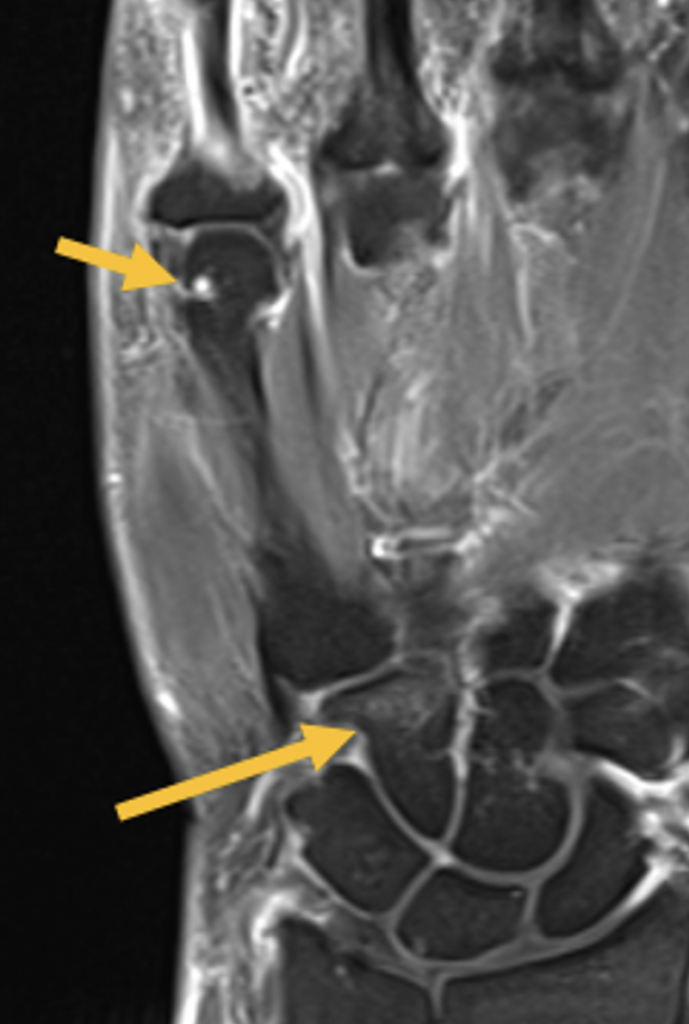

- Erosion oder kleine Zyste im MC-5 Köpfchen (kurzer Pfeil) und Knochenmarködem im Os hamatum (langer Pfeil) T1 FS KM

- Synovitis der MCP D5, PIP und DIP Gelenke D5 (Pfeile) (T1 FS KM)

- Der Hamatumbefund ist vereinbar mit einer Osteitis im Rahmen einer entzündlichen Erkrankung